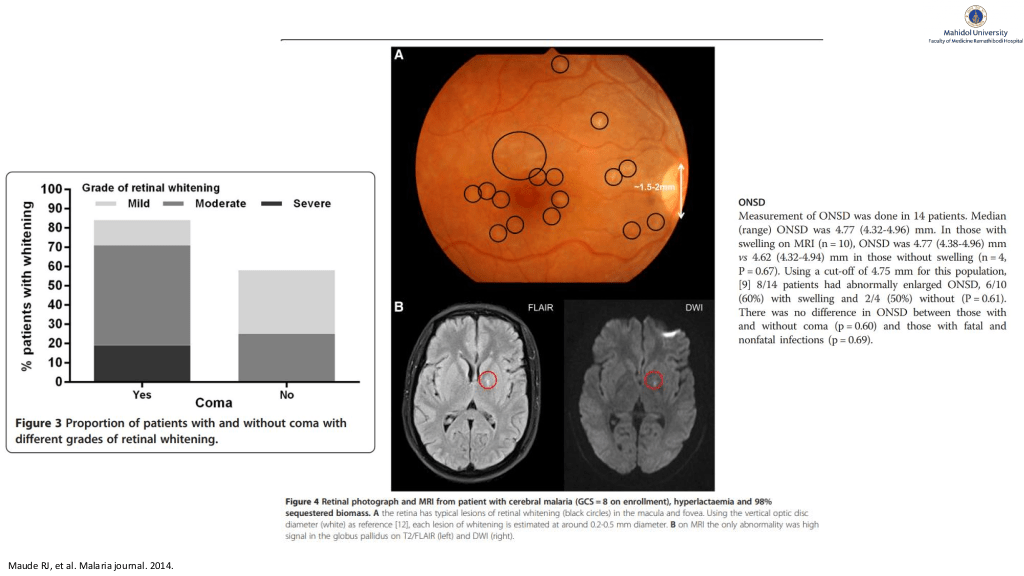

Maude RJ, et al. Malaria journal. 2014.

#40.